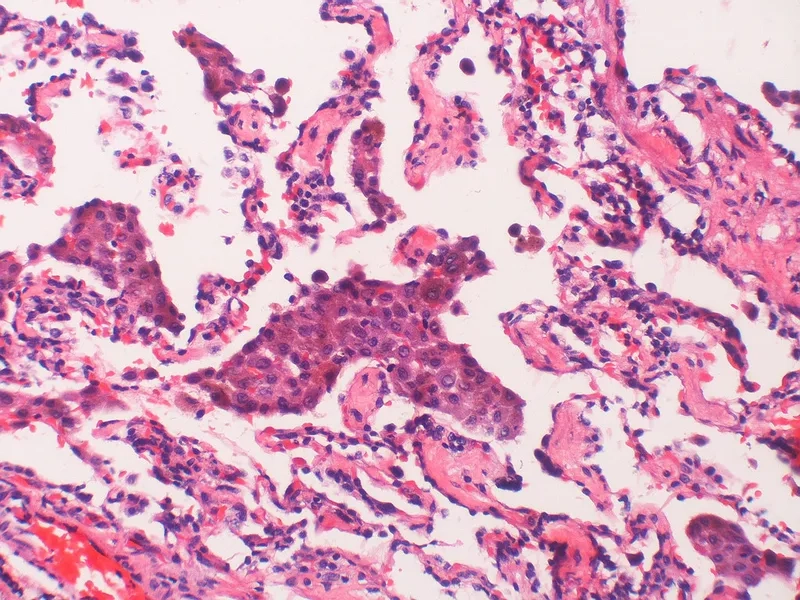

Image of the disease Lymphangioleiomyomatosis